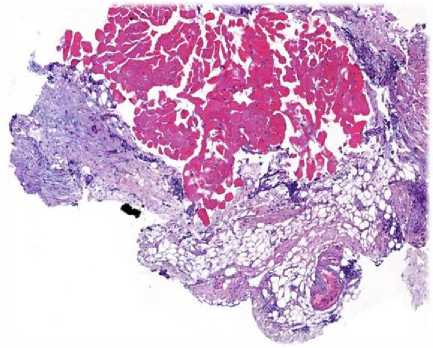

Рис. 4. Гистологические сканы перитонеальных метастазов до начала лечения (окрашивание гематоксилином и эозином, ув. ×50)

• Fig. 4.    Pre-treatment histopathological scans of peritoneal metastases (hematoxylin and eosin staining, ×50 magnification)

Рис. 7. Гистологические сканы перитонеальных метастазов после 6 курсов лечения (окрашивание гематоксилином и эозином, ув. ×50)

• Fig. 7.    Histopathological scans of peritoneal metastases after 6 treatment cycles (hematoxylin and eosin staining, ×50 magnification)